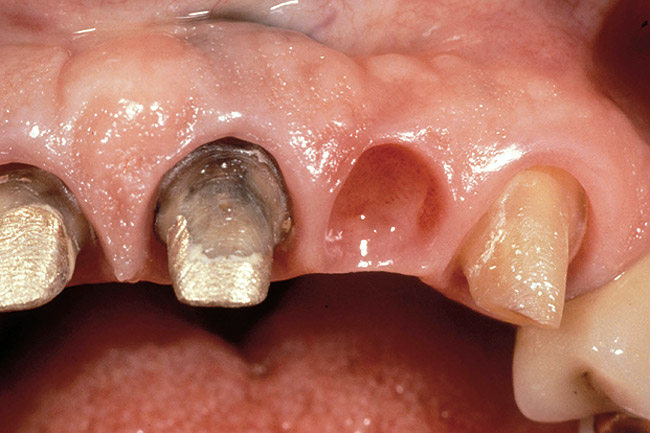

Figure 3  Dark teeth or teeth requiring restorations that are more opaque for masking often require the margin to be carried subgingivally, as with this central and lateral incisor.

Figure 3

Figure 4  View of the completed central and lateral incisor with margins placed subgingivally, but maintaining tissue health.

Figure 4

The most common reasons to extend a margin below tissue are: caries below gingiva; old restorations that already exist below gingiva; to achieve adequate tooth preparation length for proper retention and resistance; to make significant contour alterations; to hide the margin when the tooth is discolored (Figure 3 and Figure 4); and to hide the margin when the restorative material of choice demonstrates optical properties different from those of the natural tooth such that the margin would be highly visible. Regardless of why a subgingival margin is chosen, there are 2 negative responses that may occur.